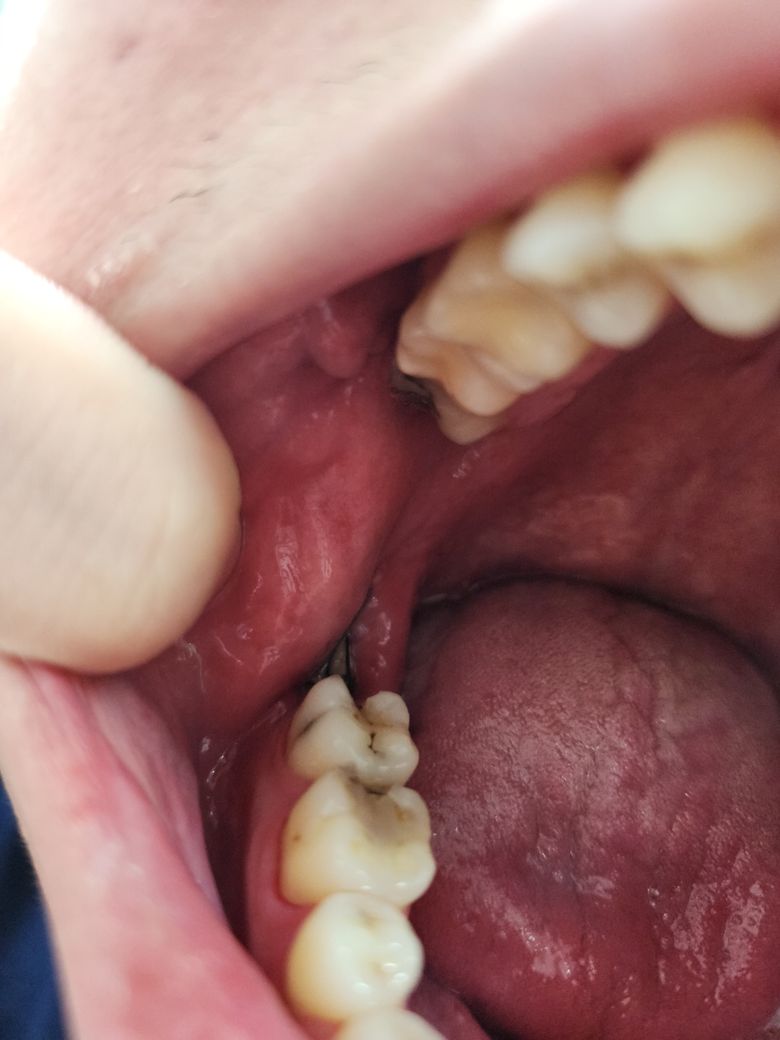

사랑니 뽑은 자리 실밥 터진거 같은데 병원가봐야할까요?

안녕하세요 2주전에 사랑니 뽑고 실밥을 연유로 못뽑다가 방금 음식먹다가 콱 잘못 씹어서 조금 아픈데 사랑니쪽 실밥쪽이 터진것같은데 괜찮은가요? 병원을 당장 갈수없어서 그런데 괜찮은 상태인지 알려주세요

사진상으로는 크게 문제될 건 없어보입니다. 이미 시간이 꽤 지나서 실밥이 풀려도 괜찮습니다.